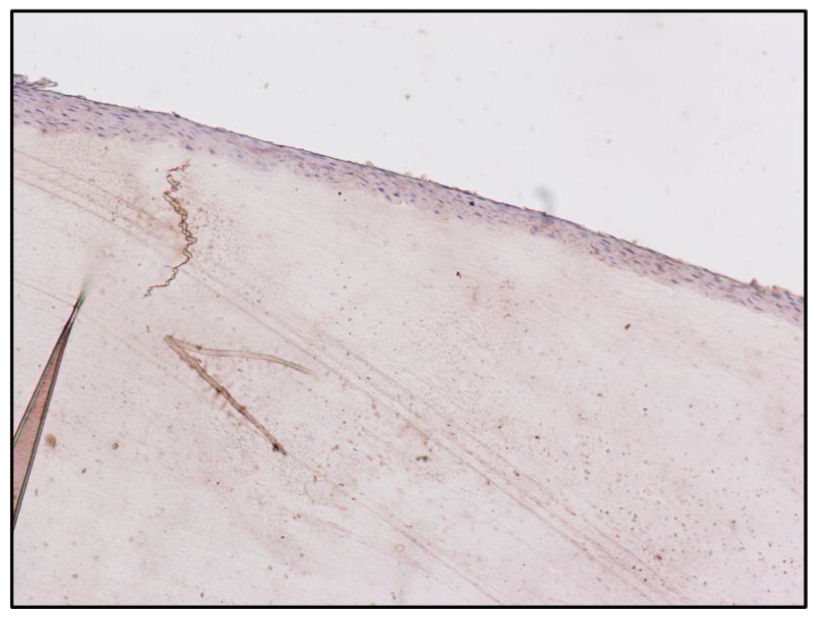

| Fingernail matrix | Area | Mean |

| Subject A (Figure 1) | 1,228,800 | 19.695 |

| Subject A matrix | Instrument | Morphine | 6-MAM | Codeine | Methadone | EDDP |

| Blood | GC-MS | 472 ng/ml | Negative | Positive | Positive | Positive |

| Scalp hair | UHPLC | 3.64 ng/mg | 1.42 ng/mg | Positive | Positive | Positive |

| Fingernail | UHPLC | 0.35 ng/mg | 0.43 ng/mg | Positive | Positive | Positive |